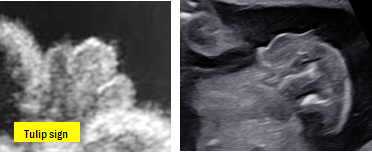

①Hypospadias: urethral orifice의 위치가 비정상일 때를 일컫습니다. 초음파 소견으로, loss of the pointed tip of penis, abnormal ventral curvature of the penis, small penile shaft, tulip sign이 관찰된다면 의심할 수 있습니다.